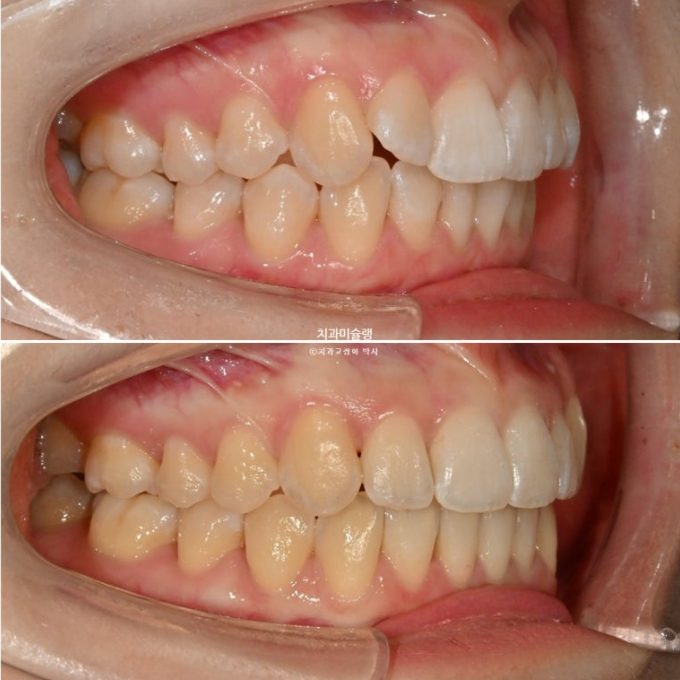

2급 교합관계를 보이는 좌측엔 교합관계 개선을 위한 악간고무줄 처방을 해서 덧니뿐아니라 교합관계개선과 주심선 개선을 도모합니다.

고무줄을 열심히 껴준 탓에 좌측 교홥관계는 좀 더 1급에 가까워졌습니다.

25.01~25.11

우측은 완벽한 1급을 달성했습니다